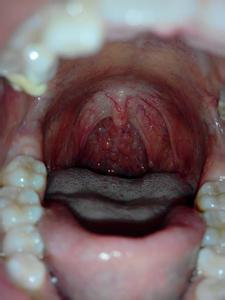

咽喉炎,感觉是反胃,买点药,或者含片坚持一段时期。